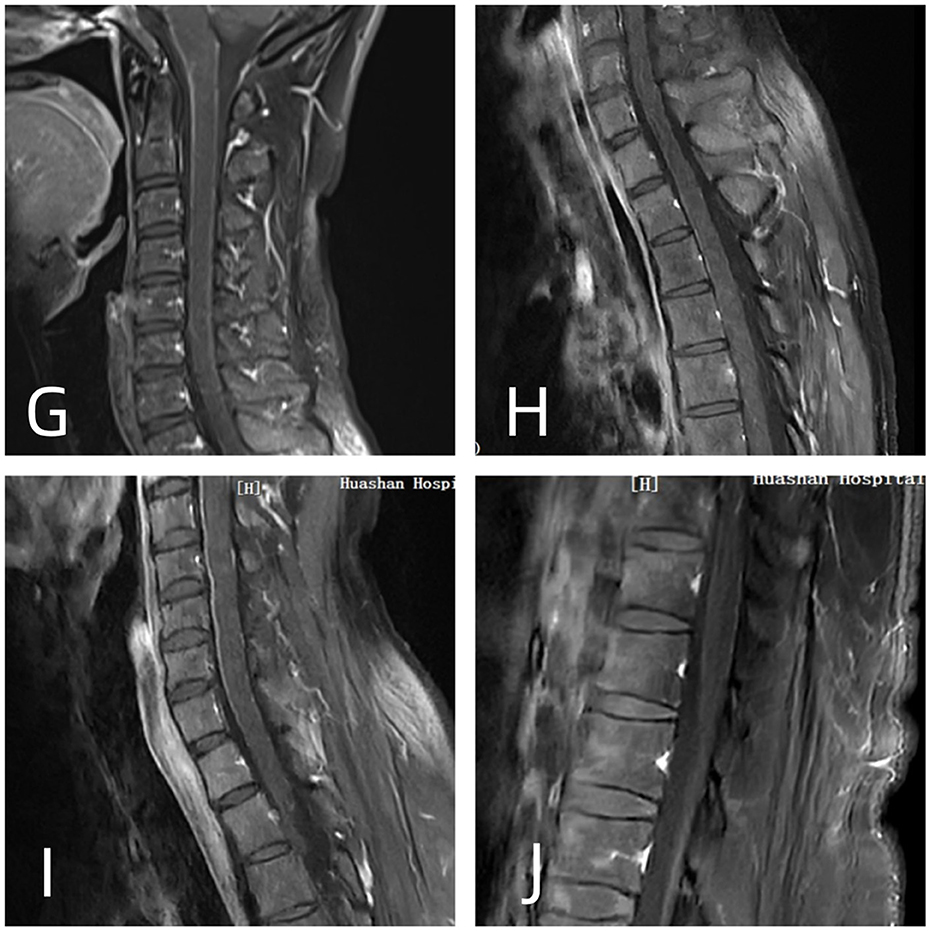

Brain MRI revealed RESLES-compatible abnormal signals in the SCC in all cases (Figure 1). Enhanced spinal MRI showed leptomeningeal enhancement in four cases (Figure 2). All patients received immunotherapy (corticosteroids, IVIG, or monoclonal antibodies), resulting in complete recovery in seven cases and neurological sequelae in five, with a maximum mRS score of 5.

Figure 2. (G, I) T1-weighted contrast-enhanced (CE-T1WI): linear enhancement of the cervical spinal cord pia mater. (H) CE-T1WI: linear enhancement of the pial membrane in the thoracic spinal cord (J) CE-T1WI: leptomeningeal enhancement around the conus.